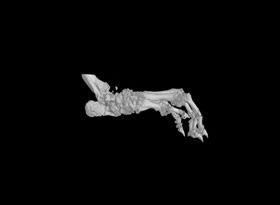

1.掃描重構:常規(guī)樣本,一個視野可以掃的樣本,按以上報價。對于一些特殊樣本或較大樣本,可能需要多個視野掃,費用按相應的視野數(shù)計算,比如大鼠爪子至少需要3個視野。

2.數(shù)據(jù)分析:如果需要做多個部位分析,需要按部位數(shù)量收費,骨密度(BMD)單獨收費。